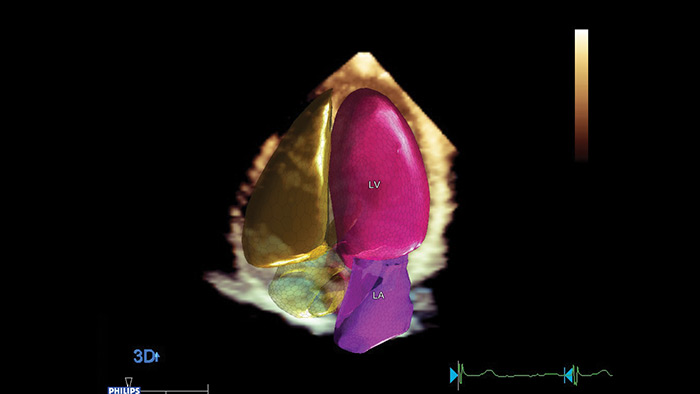

Kardiologische Quantifizierung für mehr Diagnosesicherheit Philips Dynamic HeartModelA.I. ist ein 3D-Tool, das die Ejektionsfraktion (EF) als Teil eines Routine-Arbeitsablaufs innerhalb von Sekunden zuverlässig und reproduzierbar misst.